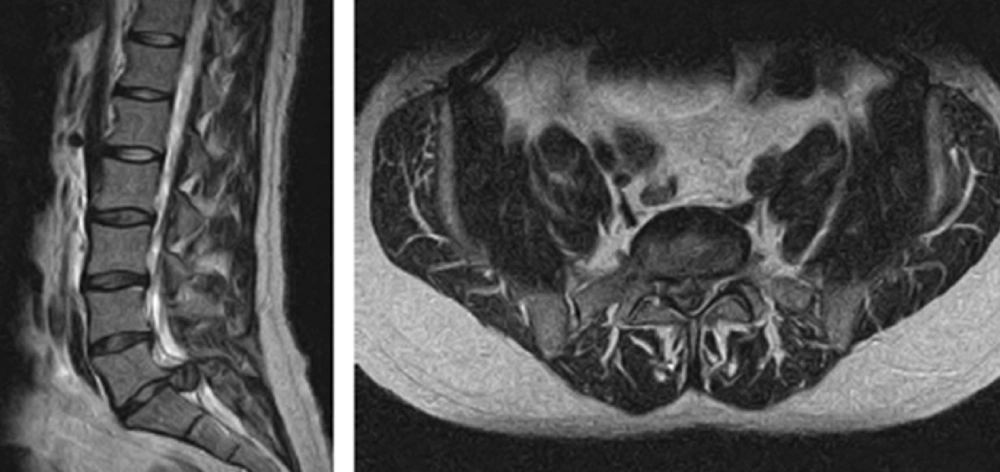

مهمترین ابزار تصویربرداری برای تأیید تشخیص، MRI ستون فقرات کمری است. این روش غیرتهاجمی بهوضوح نشان میدهد که آیا فشردگی ریشههای عصبی در کانال نخاعی وجود دارد یا خیر، و در صورت وجود، علت آن (مانند فتق دیسک، تومور یا خونریزی) مشخص میشود. در مواردی که MRI در دسترس نیست، از سیتیمیلوگرافی استفاده میشود.